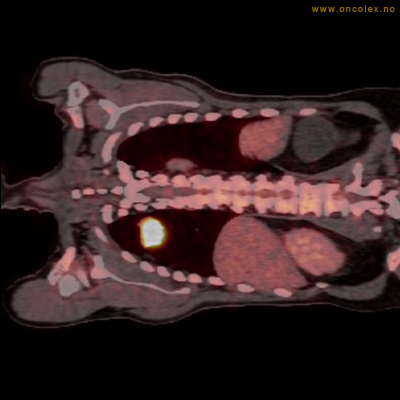

Vev som tar opp mer radioaktivt stoff, synes som hvite områder som lyser opp mer i forhold til annet vev som tar opp mindre sukker.

Kraftig opptak i svulst i lunge.

Lungekreft med spredning til lymfeknute i lungehilus.